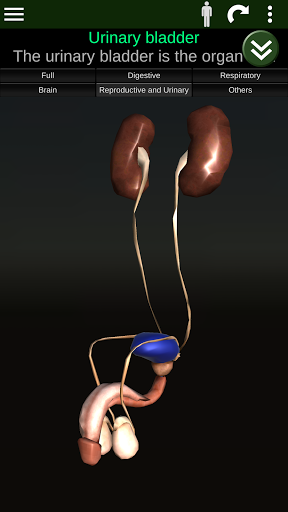

Показує 3D анатомічну модель основні органи людського тіла та опис кожного з них.

* Репродуктивна система, яка включає чоловічі та жіночі репродуктивні органи.

* Описи кожного органу.